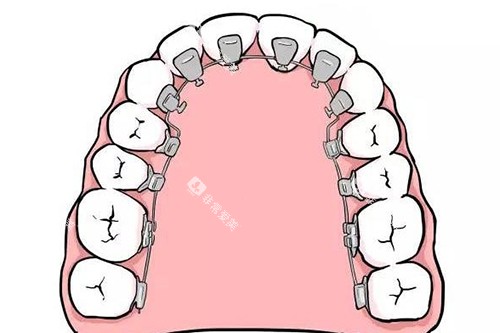

Ebrace舌侧矫正作为一种可靠的牙齿矫正技术,近年来受到了许多追求美观和个性化矫正方案患者的关注。它通过将矫治器安装在牙齿的内侧(舌侧),实现了高度的隐蔽性,几乎不影响外观。

高度隐蔽:矫治器安装在牙齿内侧,从外观上看几乎无法察觉,适合对美观要求较高的患者。

个性化定制:采用CAD/CAM技术和3D打印技术,根据患者的牙齿形态进行个性化设计,确保矫正结果和舒适度。

有效矫正:由于施力点更接近牙齿的阻抗中心,矫正过程更加有效,通常矫正周期比传统矫正更短。